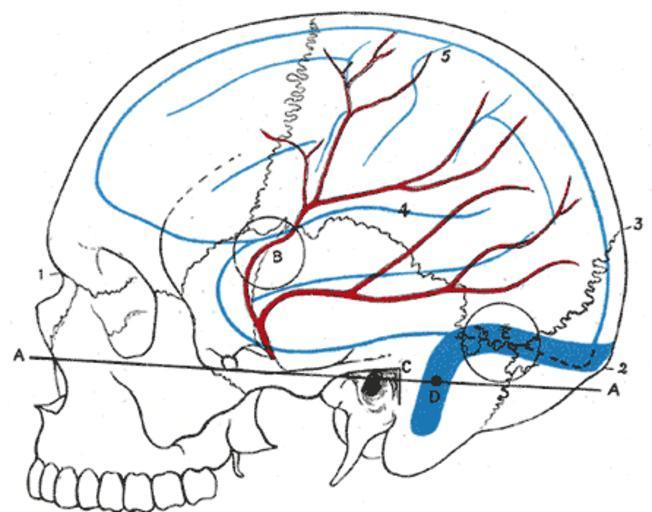

| Keywords: Gray1198.png Relations of the brain and middle meningeal artery to the surface of the skull 1 Nasion 2 Inion 3 Lambda 4 Lateral cerebral fissure 5 Central sulcus AA Reid ™s base line B Point for trephining the anterior branch of the middle meningeal artery C Suprameatal triangle D Sigmoid bend of the transverse sinus E Point for trephining over the straight portion of the transverse sinus exposing dura mater of both cerebrum and cerebellum Outline of cerebral hemisphere indicated in blue; course of middle meningeal artery in red Other fields 1 Information field Ucfirst Plate 1198 before 1858 Henry Gray Anatomy of the Human Body See Book section below 1198 Creator Henry Vandyke Carter Book Gray's Anatomy PD-old-100-1923 Gray's Anatomy plates 1198 Central sulcus Lateral sulcus Nasion | ||||